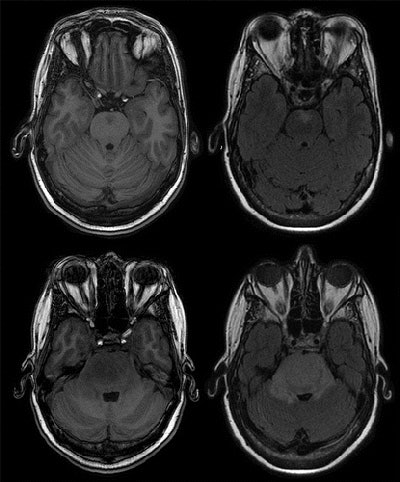

All brain MRI exams were conducted on a 1.5-tesla scanner (GE Healthcare) with identical imaging protocols for all participants at each time point of the study.

Among the total group of subjects, 549 (9.5%) had least one incidental brain finding. More abnormalities were found in women (306, 56%) than men (243, 44%).

The most common incidental finding was meningioma (143, 2.5%), a benign brain tumor that most often occurs in adults, followed by cerebral aneurysms (134, 2.3%). The two abnormalities accounted for more than half of all incidental findings.

"This may partly be from the use of our high-resolution proton density-weighted sequence, which permits a relatively good view of the circle of Willis compared with conventional T1-weighted and T2-weighted sequences and likely improved our detection of aneurysms," they wrote.

Other incidental findings included arachnoid cysts (92, 1.6%) and pituitary abnormalities (67, 1.2%).